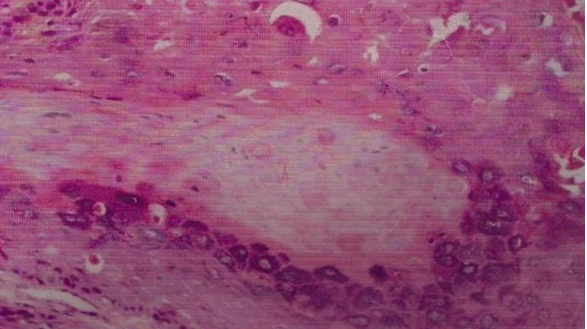

Herein, we report a case of a 40-year-old normotensive, non-diabetic, euthyroid male patient who presented with a non-healing erythematous slightly scaly plaque involving the volar and dorsal aspects of left thumb from last eight months (Figure 1) and (Figure 2). There was history of pruritus and slight burning sensation. There was a history of application of potent topical steroids for few months with no response. A punch biopsy was done which confirmed the diagnosis of eczema psoriasis and Bowen's disease. On histopathology, the patient showed thickened epidermis with full thickness dysplasia of squamous epithelium and atypical keratinocytes with numerous mitotic figures. The basement membrane was intact with no focus of invasion or solar elastosis (Figure 3) and (Figure 4). Thus a diagnosis of Bowen's disease was made. The patient was put on topical 5-fluorouracil and is doing well. | ||||||

Bowen's disease (BD) is a form of intra-epidermal or in-situ squamous cell carcinoma with a small potential for invasive malignancy, and commonly involves chronically photo-exposed areas, especially head and neck region. Commonly a persistent, non-elevated erythematous scaly and crusted plaque is seen. Bowen's disease may occur at any age in adults, but is rare before the age of 30 years; most patients are aged over 60. Any site may be affected, although involvement of palms or soles is uncommon. Bowen's disease occurs predominantly in women in whom about 60-85% of patients have lesions on the lower leg, usually in previously or presently sun-exposed areas of skin. Chronic ultraviolet radiation exposure, arsenic exposure, human papillomavirus and immunosuppression are the various aetiological factors [1] [2] [3]. Histopathology is characterized by full-thickness dysplasia of the epidermis, with loss of the normal maturation of its components. Keratinocytes are atypical and disorderly, often described as having a windblown appearance. Basement membrane is intact. Topical 5-fluorouracil, imiquimod, photodynamic therapy, cryotherapy and excision are the various treatment modalities [4]. | ||||||